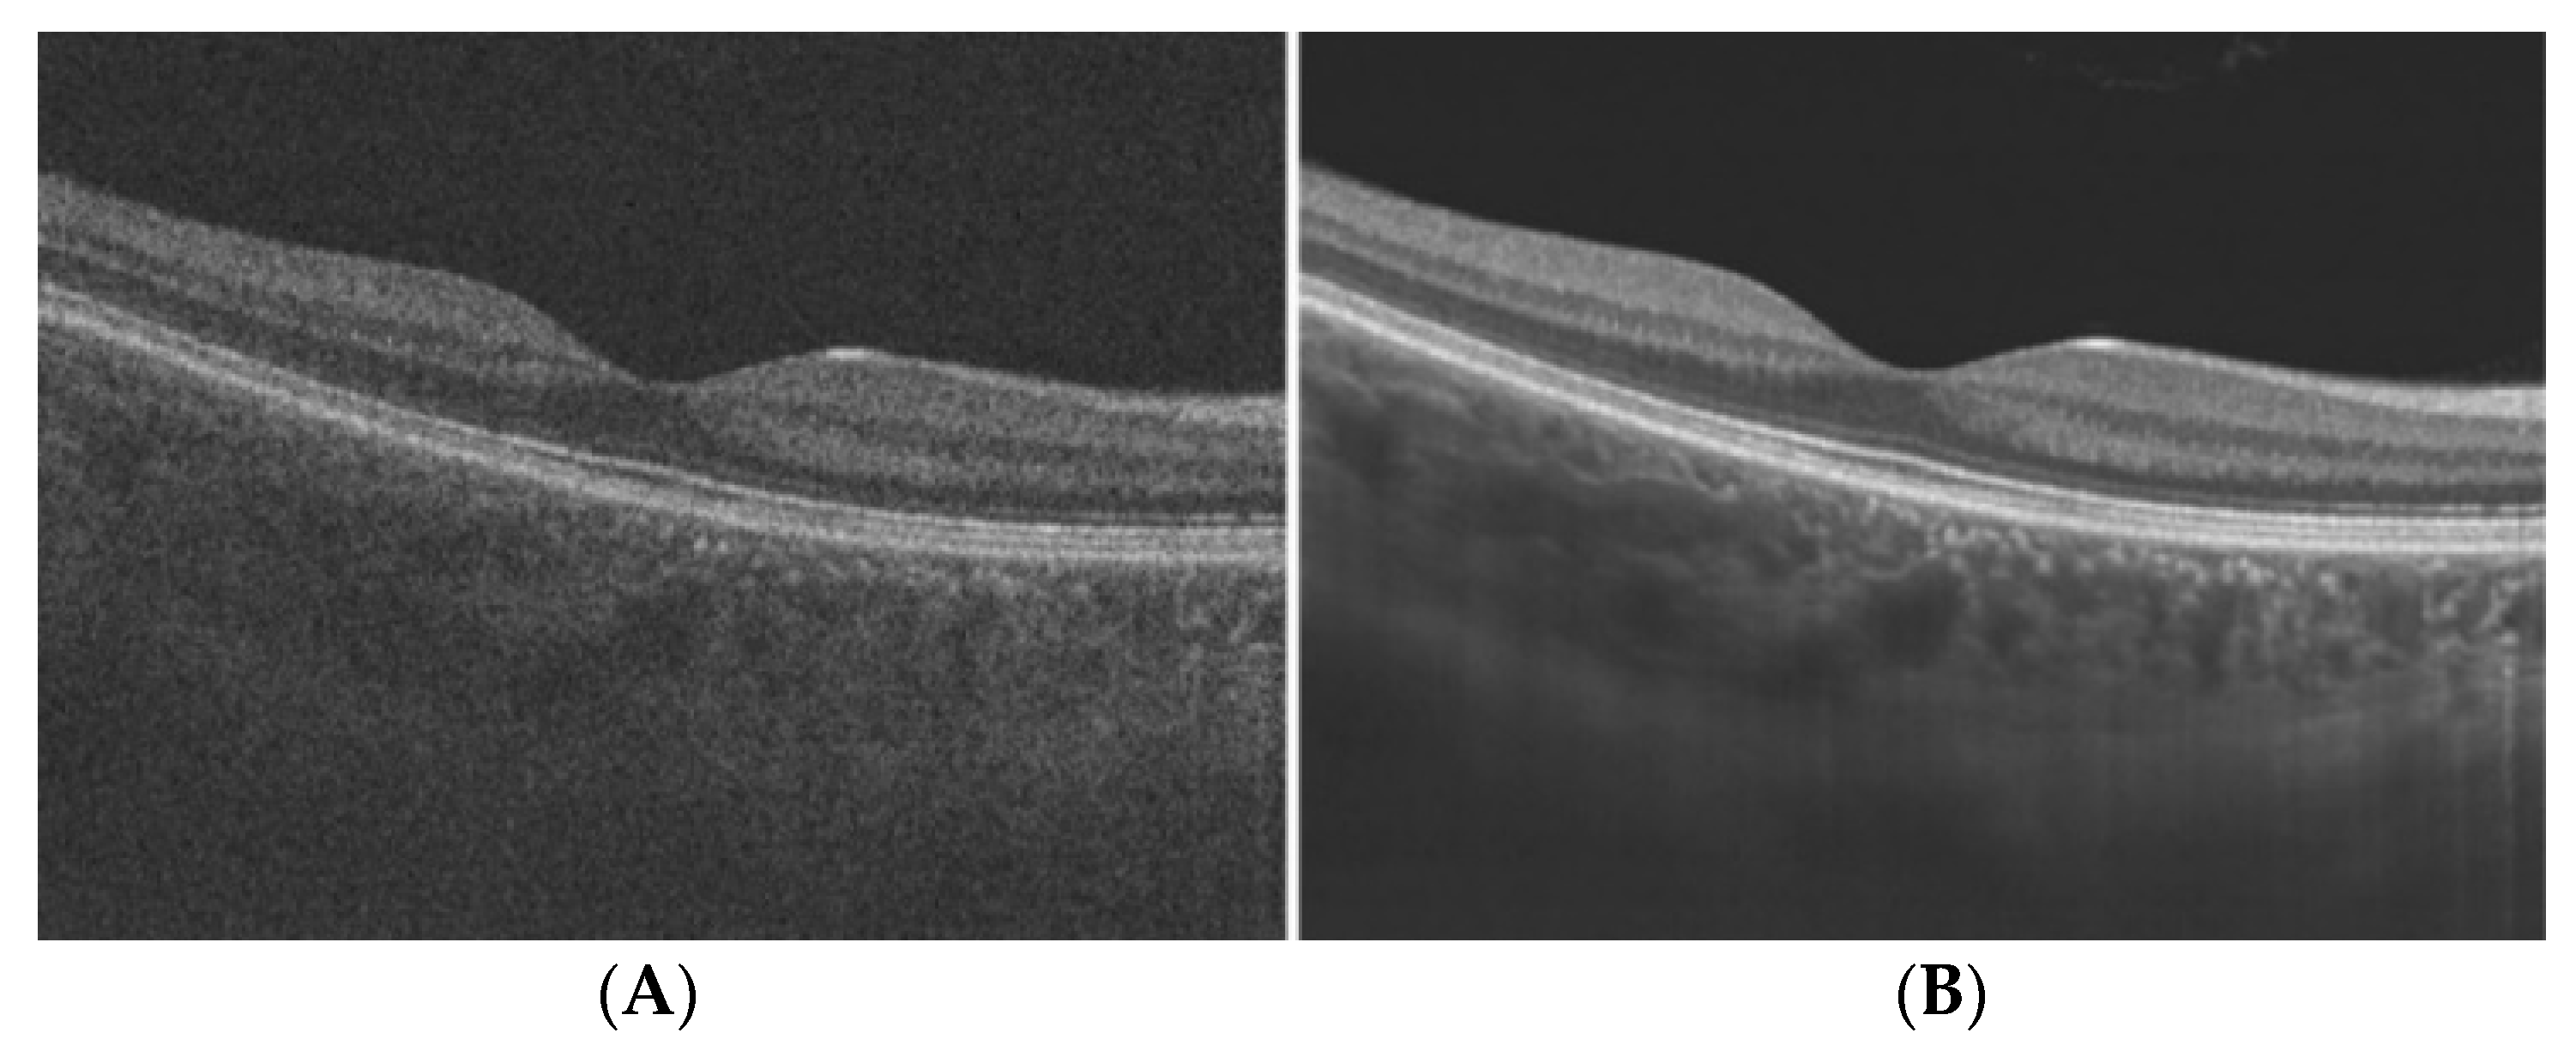

| PVD | An early sign of macular 0edema and lamellar macular hole |

- Bhende, M.; Shetty, S.; Parthasarathy, M.K.; Ramya, S. Optical Coherence Tomography: A Guide to Interpretation of Common Macular Diseases. Indian J. Ophthalmol. 2018, 66, 20–35. [Google Scholar] [CrossRef] [PubMed]